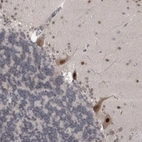

Immunohistochemical staining of human cerebellum shows strong nuclear positivity in Purkinje cells.